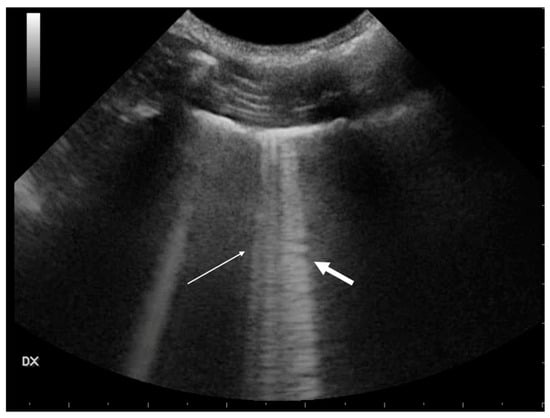

3.1.1. Pneumothorax

- Lichtenstein, D.; Mezière, G.; Biderman, P.; Gepner, A. The “lung point”: An ultrasound sign specific to pneumothorax. Intensive Care Med. 2000, 26, 1434–1440. [Google Scholar]

- Santos-Silva, J.; Lichtenstein, D.; Tuinman, P.R.; Elbers, P.W.G. The lung point, still a sign specific to pneumothorax. Intensive Care Med. 2019, 45, 1327–1328. [Google Scholar] [CrossRef] [PubMed]

- Lichtenstein, D.A.; Mezière, G.; Lascols, N.; Biderman, P.; Courret, J.P.; Gepner, A.; Goldstein, I.; Tenoudji-Cohen, M. Ultrasound diagnosis of occult pneumothorax. Crit. Care Med. 2005, 33, 1231–1238. [Google Scholar] [CrossRef]

- Boysen, S.; McMurray, J.; Gommeren, K. Abnormal curtain signs identified with a novel lung ultrasound protocol in six dogs with pneumothorax. Front. Vet. Sci. 2019, 6, 291. [Google Scholar] [CrossRef] [PubMed]